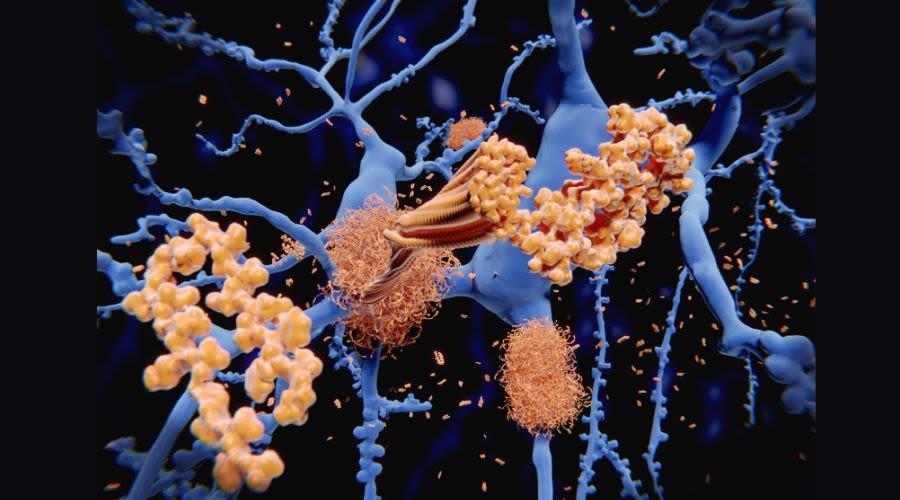

Scanning ultrasound can remove amyloid plaques and restore brain function

It was surprising yet rewarding to find that scanning ultrasound can reduce the signs of dementia — a discovery we have now taken into a human safety trial.